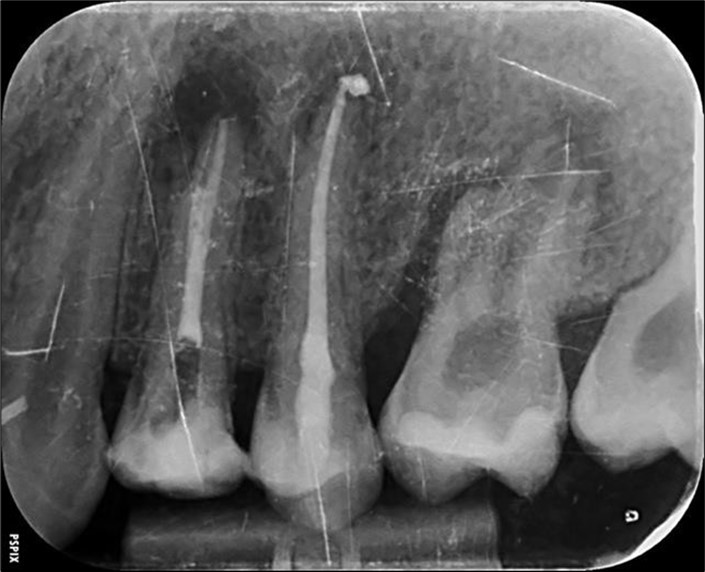

Periapical radiography (phosphorus number 2 plaque and X-MIND® Unity; Acteon) and cone-beam computed tomography (X-MIND® 3D; Acteon) (80 × 80, 150 Micron) were performed and showed periapical lesions on teeth 14, 15, 16, 24, 25, 26, 35, 36, and 46, as well as advanced endo-perio lesions on teeth 26 and 16. orthopantomogram (X-MIND® 3D; Acteon) and bitewings (phosphorus number 2 plaque and X-MIND® Unity; Acteon) also showed wide pulp chambers and roots canals. Figure 1, Figure 2

Figure 1.1 and 2 show a wide pulp chamber, root canals, and several restorations.

Figure 2.2. 3, 4, and 5 show periapical lesions on teeth 15, 16, 24, 25, 26, 35, 36, and 46.